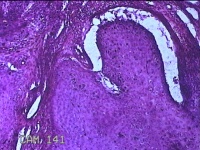

额部肿物

性别

女

年龄

32岁

临床诊断

寻常疣

一般病史

额部起疹1年,不痒。

标本名称

大体所见

灰白暗红色肿物0.7x0.5x0.2cm一个,表面光滑,切开肿物呈实性,切面灰白粉红色,质软。